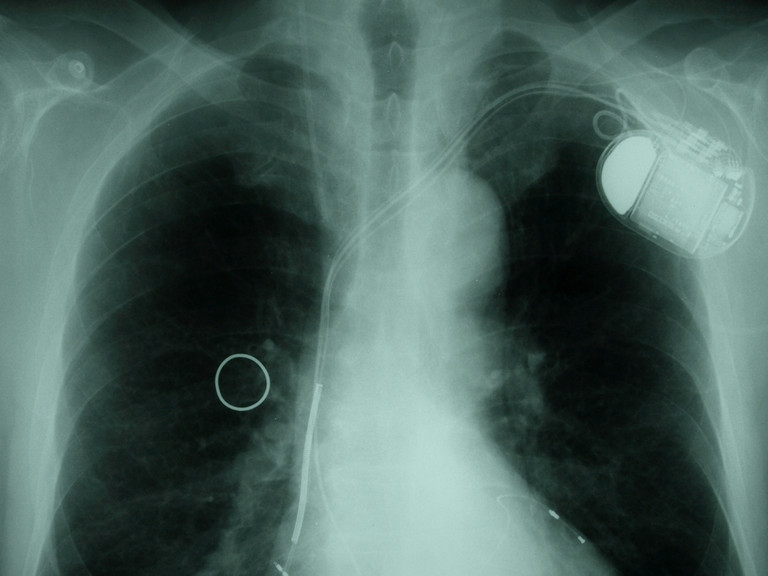

Cardiovascular Medicine